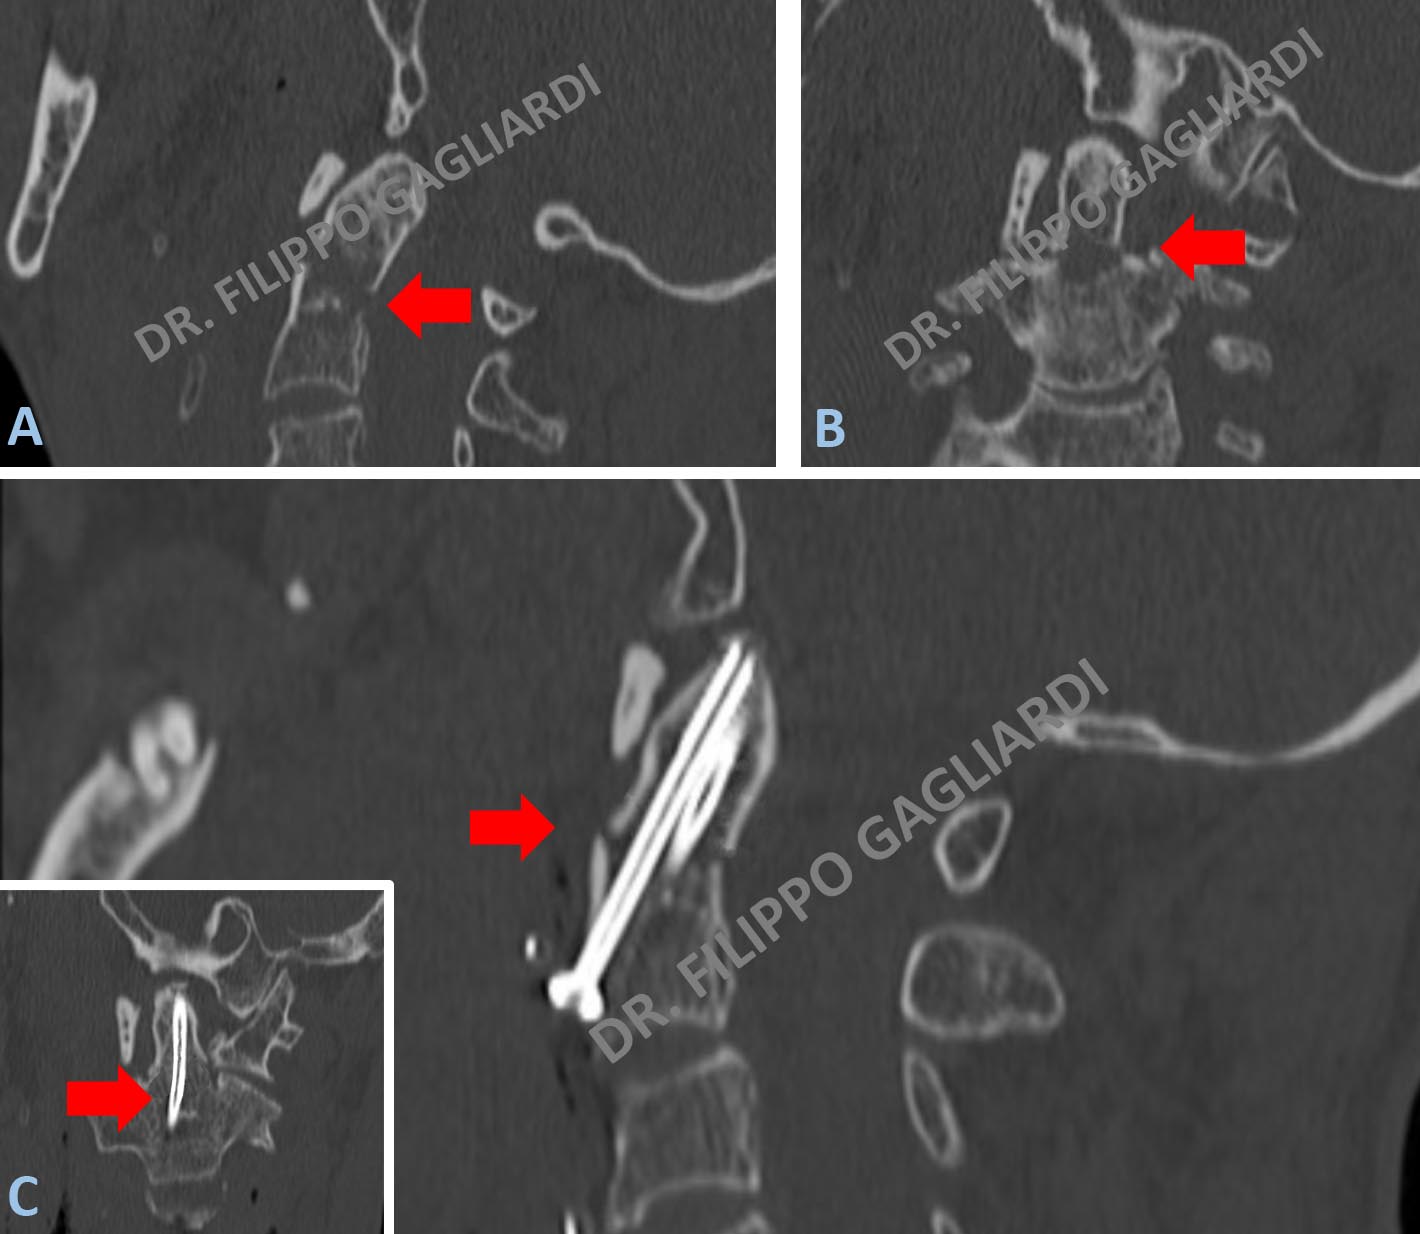

Caso di frattura del dente dell’epistrofeo (seconda vertebra cervicale) (frecce rosse in Figure A e B). Condizione a potenziale rischio di vita; la dislocazione del frammento potrebbe infatti determinare la compressione dei centri nervosi che regolano la respirazione. Il Paziente è stato sottoposto al posizionamento di due viti di riduzione della frattura. Si é proceduti con una tecnica definita “avvitamento del dente dell'epistrofeo per via anteriore”. Consiste nell’approcciare la colonna vertebrale cervicale dal davanti con una piccola incisione del collo passando quindi posteriormente alla faringe. Le viti hanno consentito di avvicinare i frammenti ed immobilizzarli in modo tale da consentirne la fusione e la formazione del callo osseo (frecce rosse in Figura C).

Stabilizzazione cervicale Caso di avvitamento per via anteriore del dente dell’epistrofeo (seconda vertebra cervicale) per una frattura con dislocazione del frammento all’interno del canale spinale contro il midollo spinale (Figura A). Immagine intraoperatoria (Figura B). Risultato post-operatorio (Figura C). Si vede la vite correttamente posizionata con la riduzione e la sintesi della frattura.